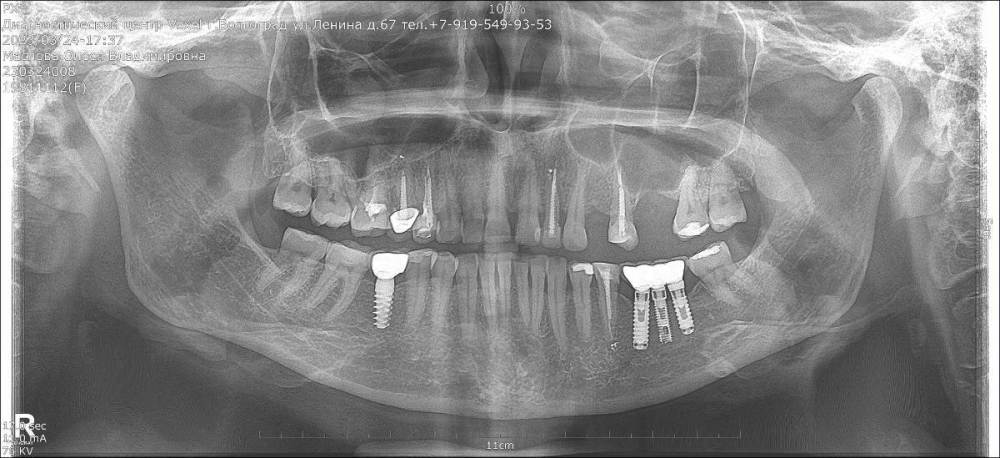

Важная Опубликовано 1 мая, 2023 Поделиться Опубликовано 1 мая, 2023 Добрый день. На верхней челюсти стоит временный протез на имплантатах или временные коронки на 8-ми имплантах, не знаю, как правильно сказать. На нижней челюсти поставила у другого доктора на трех импланта остем мост из четырех зубов, мост из диоксида циркония, доктор поставил прикрутил и поставил на временный цемент, сказал через неделю прийти посмотреть , как будет стоять и поставить постоянно, через неделю, его ученик вычищал временный цемент и вдруг отломился один зуб от моста, доктор сказал, что так как вверху стоит временный протез, то трудно правильно сделать низ, нужно делать и верх и низ одновременно, а я теперь боюсь делать, может у него качество коронок плохое? Коронки из диоксида циркония. Жевательные зубы. Доктор сказал, что это очень прочный материал, но он же сломался. Стоит ли мне вообще у него ставить коронки? Ссылка на комментарий

olesya.1211 Опубликовано 26 мая, 2023 Поделиться Опубликовано 26 мая, 2023 Здравствуйте! Скажите пожалуйста, что в моем случае лучше установить в место отсутствия 24го зуба: имплант или сделать мостовидный протез? Фото прилагаю. Проблема состоит в том, что 26й зуб был лечен резорцин-формалиновой пастой и его удалили с перфорацией дна гайморовой пазухи больших размеров, была лоскутная операция и кость так и не наросла. Если ставить имплант на 24й зуб, то со временем, когда удалю еще 25й, то сделать мост уже не смогу, так как имплант с родными зубами в мост не объединяют. В области 26го зуба планирую мост делать, а опорные зубы долго не стоят, поэтому и задаюсь сейчас таким вопросом. Еще и 22й зуб-киста 2 раза леченная, держится на одном штифте вся пломба практически, тоже скоро удалю, слегка шатается, а кость впереди тонкая, имплант без подсадки кости тоже там не поставишь. Подскажите пожалуйста что выбрать. Ссылка на комментарий